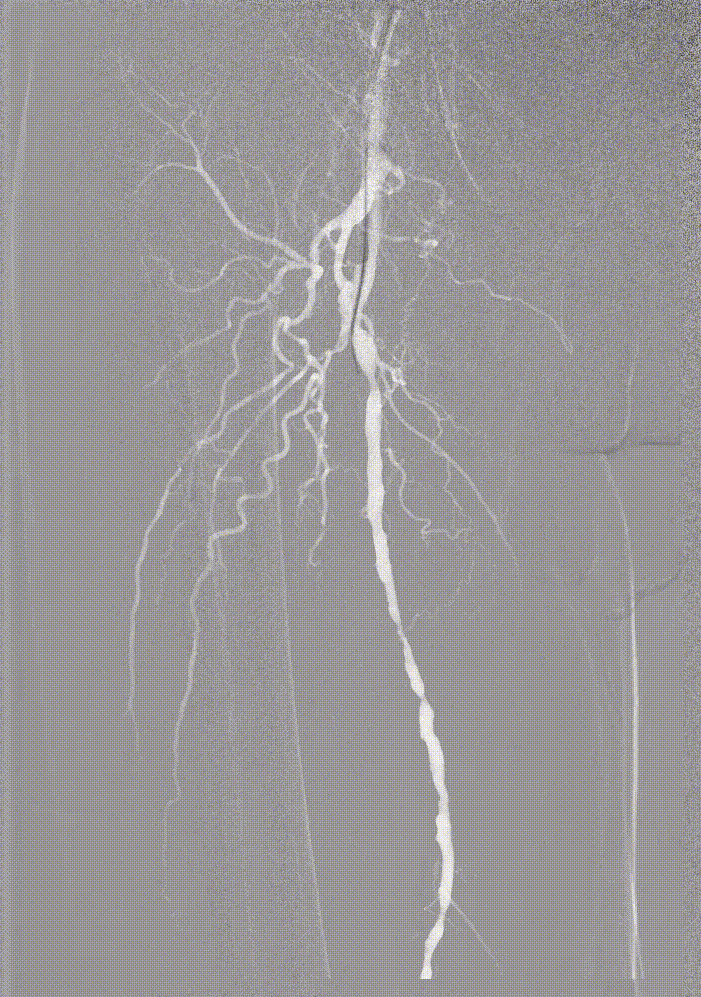

IVUS提示病变段仍有局部重度狭窄,遂选择最新上市的”始祖鸟”紫杉醇药物涂层球囊(5*150mm、6*150mm )对残余狭窄进行扩张

IVUS提示病变段仍有局部重度狭窄,遂选择最新上市的”始祖鸟”紫杉醇药物涂层球囊(6*150mm、 5*150mm ) 分别对股浅动脉、腘动脉、胫腓干动脉逐段扩张,压力至工作压维持3分钟。

步进造影配合血管腔内超声诊断导管提示:股浅动脉全程、腘动脉、胫腓干动脉血流通畅,未见明显夹层、造影剂外溢,远端未见栓塞,膝下动脉如前。